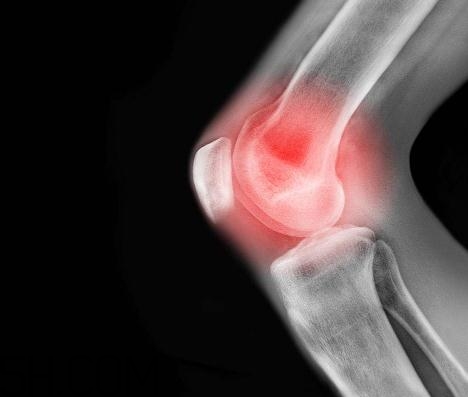

患有關(guān)節(jié)炎的人在飲食上面要特別注意,很多東西都會(huì)加重病情,要注意忌口。今天5號(hào)網(wǎng)小編給大家講講關(guān)節(jié)炎能吃螃蟹嗎?關(guān)節(jié)炎能吃海鮮嗎?

螃蟹性寒,一般關(guān)節(jié)炎患者忌食海鮮類食物,這其中自然包括螃蟹。尤其是風(fēng)濕性關(guān)節(jié)炎和類風(fēng)濕關(guān)節(jié)炎患者,更加要避免吃海鮮類,在關(guān)節(jié)炎的急性發(fā)作期、關(guān)節(jié)紅腫灼熱時(shí),更加不宜吃螃蟹,也不宜吃海鮮。

海鮮類的食品是需要風(fēng)濕性關(guān)節(jié)炎的患者忌口的,患者不宜多吃海產(chǎn)品,海產(chǎn)品含有尿酸,被人體吸收后,能在關(guān)節(jié)中形成尿酸鹽結(jié)晶,使風(fēng)濕性關(guān)節(jié)炎的癥狀加重。

海鮮中含有大量的血尿酸,人如果吃了大量的海魚、螃蟹、海菜等海味,就會(huì)導(dǎo)致體內(nèi)血尿酸的代謝紊亂。血尿酸過多又排泄不出的話,就會(huì)在關(guān)節(jié)部位形成尿酸鹽結(jié)晶,使關(guān)節(jié)炎的癥狀更加嚴(yán)重,甚至引發(fā)痛風(fēng)。因此,關(guān)節(jié)炎患者忌多吃海鮮。